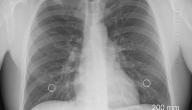

يُعرف بضع الصدر (Thoracotomy) بأنَّه الإجراء الجراحي الذي ينطوي على إجراء شقّ في جدار الصدر في المنطقة الواقعة بين أضلاع القفص الصدري، سواءً في الجانب الأيمن أم الأيسر من الصدر، بُغية الوصول إلى الرئتين أو الأعضاء الأخرى الموجودة داخل التجويف الصدري، كالقلب، والمريء، والحجاب الحاجز، والشريان الأبهر.[٢][٤]

• الانخماص الرئوي (Collapsed lung): تعرف هذه الحالة أيضًا بالاسترواح الصدري، وهي المُشكلة الصحيَّة الناتجة عن احتباس الهواء بين الرئة وجدار الصدر، فينجم عنها ألم حاد، وتزداد خطورة حدوث الاسترواح الصدري عند إزالة الأنبوب من الصدر بعد الجراحة.

• الإصابة بذات الرئة (Pneumonia): تعرف أيضًا بالالتهاب الرئوي، وقد يُساعد التَّنفس العميق وتمارين التنفس والسُّعال على تقليل خطورة حدوث هذه المشكلة.